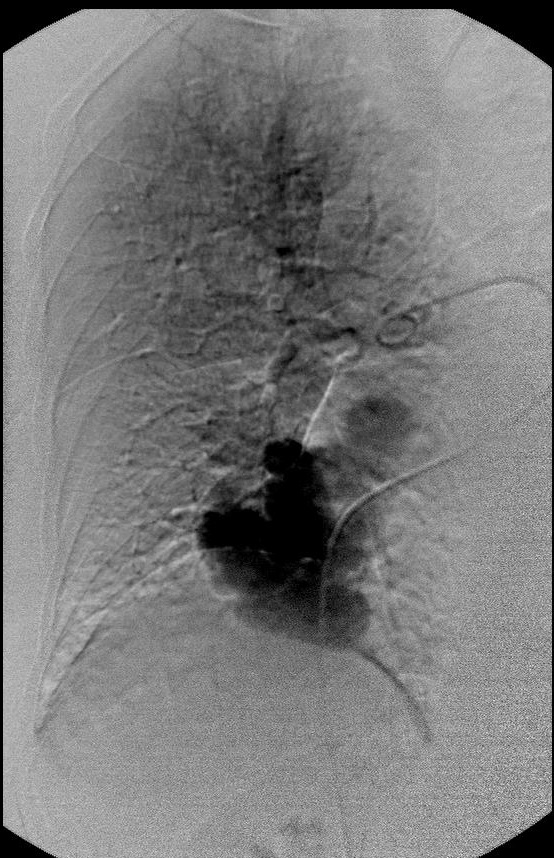

|

|

|

|

选择性进入滋养动脉 |

栓塞后弹簧栓子逸出至右肺静脉 |

栓塞后弹簧栓子逸出至右肺静脉 |

|

|

|

|

|

弹簧栓子在左心房“狂”跳 |

没啦? |

|

|

|

|

去哪儿啦? |

在这儿! |

造影 |

|

|

|

|

嵌在股深浅动脉分叉处 |

弹簧栓子被移除 |

继续栓塞 |